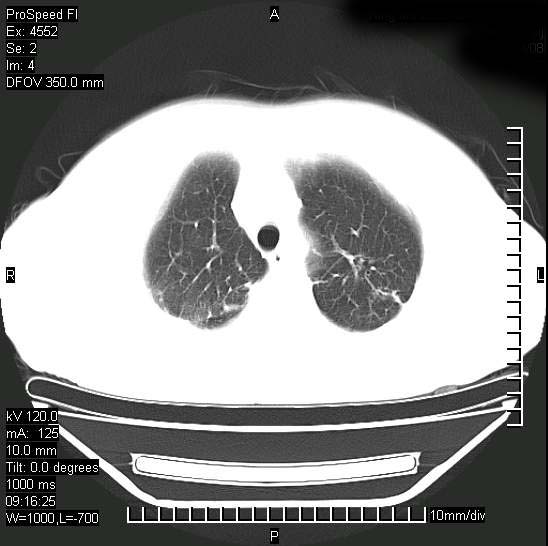

十几年前曾患肺结核,一周前突咳血约100ml,中性粒细胞稍高,诊断两上肺陈旧结核,下肺炎症,给予抗炎治疗,近几日晚上高热,39度,仍咳少量血,4天前ct及今天ct上传。

今天ct

短短几天内,病变范围明显增多扩大,以左侧明显,而且双侧出现胸水,还是考虑感染.

短短几天内,病变范围明显增多扩大,以左侧明显,而且双侧出现胸水,我更多考虑左侧中心性肺癌并并阻塞性不张及肺炎,炎症变化也太快了!

无论是肿瘤还是炎症4天的时间都发展够快的,并且还在治疗中,如果说是左肺癌那么右肺的病变不好解释,本人更加倾向于炎症,左肺舌叶支气管被痰栓或血凝块堵塞,造成阻塞性肺炎。

1)两肺结核并感染。2)不排除左肺上叶中央型肺癌并阻塞性肺炎、肺不张可能;建议行纤支镜检查。3)右肺门及纵隔淋巴结肿大。4)双侧胸腔积液。